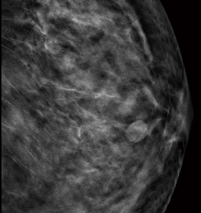

■症例2:dense breastの中のmass

症例2:2D画像(所見部分拡大) |

症例2:トモシンセシス静止画像 |

症例2:左CCの2D画像 |

症例2:左CCのトモシンセシス静止画像(11スライス目) |

症例2:左MLOの2D画像 |

症例2:左MLOのトモシンセシス静止画像(19スライス目) |